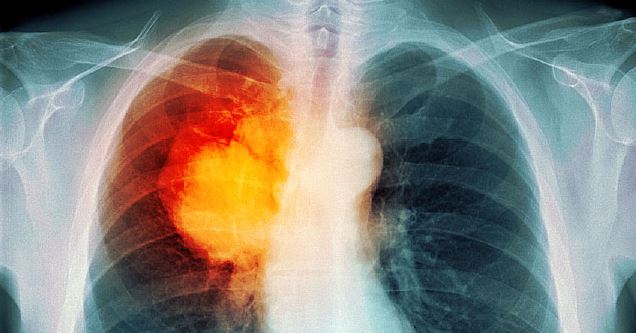

ഖത്തറിൽ ശ്വാസകോശ കാൻസറിനു പ്രധാന കാരണം പുകയില

ഖത്തറിൽ കാൻസറുമായി ബന്ധപ്പെട്ട മരണത്തിൽ 16 ശതമാനവും ശ്വാസകോശവുമായി ബന്ധപ്പെട്ടതാണെന്നും ശ്വാസകോശ കാൻസറിനു 90 ശതമാനവും പുകയിലയാണു കാരണമെന്നും റിപ്പോർട്ട്.

പുക വലിക്കാതിരിക്കുക എന്നതാണു ശ്വാസകോശ കാൻസർ വരാതിരിക്കാനുള്ള പ്രധാന പ്രതിരോധമെന്ന് കാൻസർ ചികിത്സാ മേഖലയിൽ പ്രവർത്തിക്കുന്നവർ പൊതു ജനങ്ങളെ ഓർമ്മപ്പെടുത്തുന്നു.